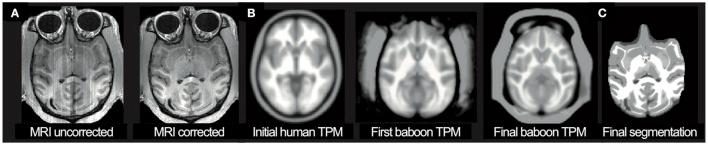

Premature Brain Aging in Baboons Resulting from Moderate Fetal Undernutrition.

Contrary to the known benefits from a moderate dietary reduction during adulthood on life span and health, maternal nutrient reduction during pregnancy is supposed to affect the developing brain, probably resulting in impaired brain structure and function throughout life. Decreased fetal nutrition delivery is widespread in both developing and developed countries, caused by poverty and natural disasters, but also due to maternal dieting, teenage pregnancy, pregnancy in women over 35 years of age, placental insufficiency, or multiples. Compromised development of fetal cerebral structures was already shown in our baboon model of moderate maternal nutrient reduction. The present study was designed to follow-up and evaluate the effects of moderate maternal nutrient reduction on individual brain aging in the baboon during young adulthood (4-7 years; human equivalent 14-24 years), applying a novel, non-invasive neuroimaging aging biomarker. The study reveals premature brain aging of +2.7 years ( < 0.01) in the female baboon exposed to fetal undernutrition. The effects of moderate maternal nutrient reduction on individual brain aging occurred in the absence of fetal growth restriction or marked maternal weight reduction at birth, which stresses the significance of early nutritional conditions in life-long developmental programming. This non-invasive MRI biomarker allows further longitudinal tracking of individual brain aging trajectories to assess the life-long effects of developmental and environmental influences in programming paradigms, aiding preventive and curative treatments on cerebral atrophy in experimental animal models and humans.